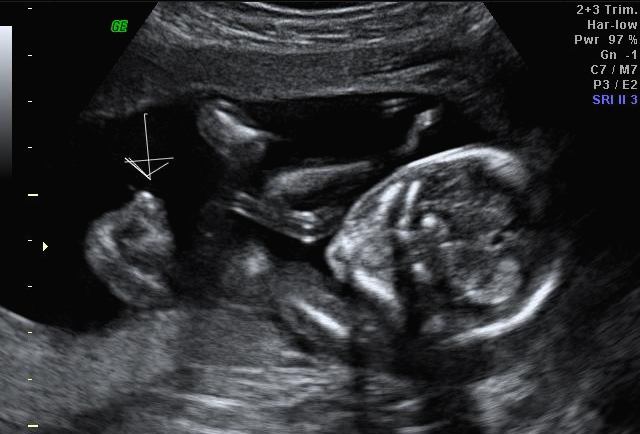

24주 차에 다시 사설로 초음파 검사를 받으러 갔는데 초음파를 보시더니 정밀 초음파 검사 때 성별 딸이 었냐 아들이 었냐 물어보시길래 딸이라고 말을 하니 미안하다고 지금 보니 딸이라고 하길래 이때는 정밀 초음파 검사 후 한 달 뒤여서 상관없다고 ㅋㅋㅋㅋㅋ 아들인지 딸인지 뭐가 중요하냐고 아이만 건강하면 된다고 하니 ㅎㅎ 그때서야 웃으시더라고요 ㅎㅎ 많이 미안했던 모양... 워낙 아이 건강상태를 꼼꼼하게 잘 봐주시고 만족할만하게 아이 얼굴 초음파 사진을 찍어주셔서 다 용서가 됐어요 ㅎㅎ

내 뱃속에 이렇게 사랑스러운 아이가 있다니 >. < 이렇게 이쁜 아이를 보면 성별반전은 중요하지 않아요~

입체 초음파 사진은 항상 만족스러워요! 사진 보면 벌써 태어난 아기처럼 어찌 이리 이목구비 뚜렷하고 아이 얼굴이 선명하게 잘 보이는지~ 제아이라 이렇게 사랑스러운 걸까요~? ㅋㅋㅋ